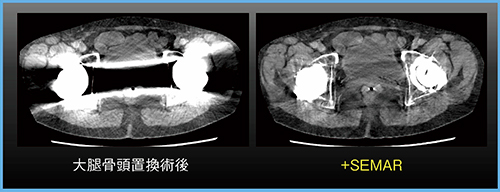

金属アーチファクトについては,金属アーチファクト低減処理機能“SEMAR(Single Energy Metal Artifact Reduction)”処理を行うことで,特にダークバンドアーチファクトを大幅に低減できる(図3)。頭頸部領域では,義歯による金属アーチファクトが問題になることが多く,当院では必ずSEMAR処理を行うようにしている。

図3 金属アーチファクト低減処理機能SEMAR